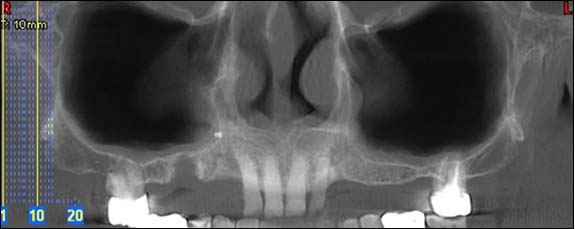

Cette radio permet d'appréhender l'ensemble de votre dentition et des structures adjacentes.

Reconstruction panoramique